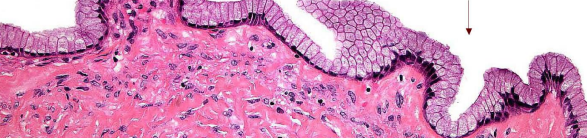

whats this

Mucinous cystadenoma (mucin secreting simple columnar epithelium with connective tissue stroma)